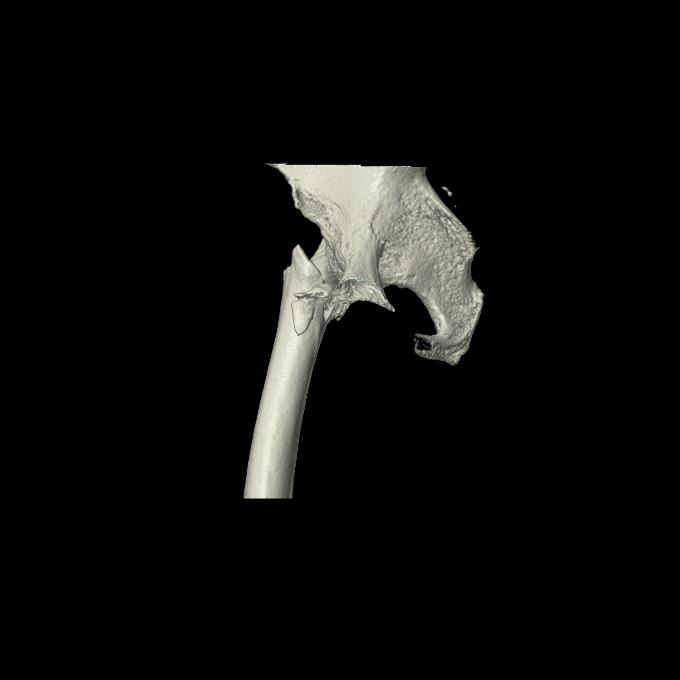

110286 2/17 股関節 2R 74歳女性 右人工骨頭

46666 1/28 両股正面+軸と 1/26 右手関節 2R 76歳女性 右転子部骨折

37 1/18 両股正面+軸 1/22 2R 86歳女性 右転子下

82084 1/14 1/20 股関節 2R 78歳男性 右人工骨頭

102811 1/13 股関節 2R 1/19 2R 80歳女性 右DHS

91569 3/25 両股正面とラウエン 70歳女性 人工骨頭+バンクーバー